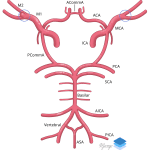

- Large volume acute subarachnoid hemorrhage throughout the right greater than left cerebral hemispheres with the largest concentration of hemorrhage in the right sylvian fissure and suprasellar cistern

- MCA aneurysm rupture

Large volume acute subarachnoid hemorrhage concerning for ruptured aneurysm with distribution suggesting a source from the right ICA terminus or right MCA. Recommend neurosurgery consultation and head CTA for further evaluation.